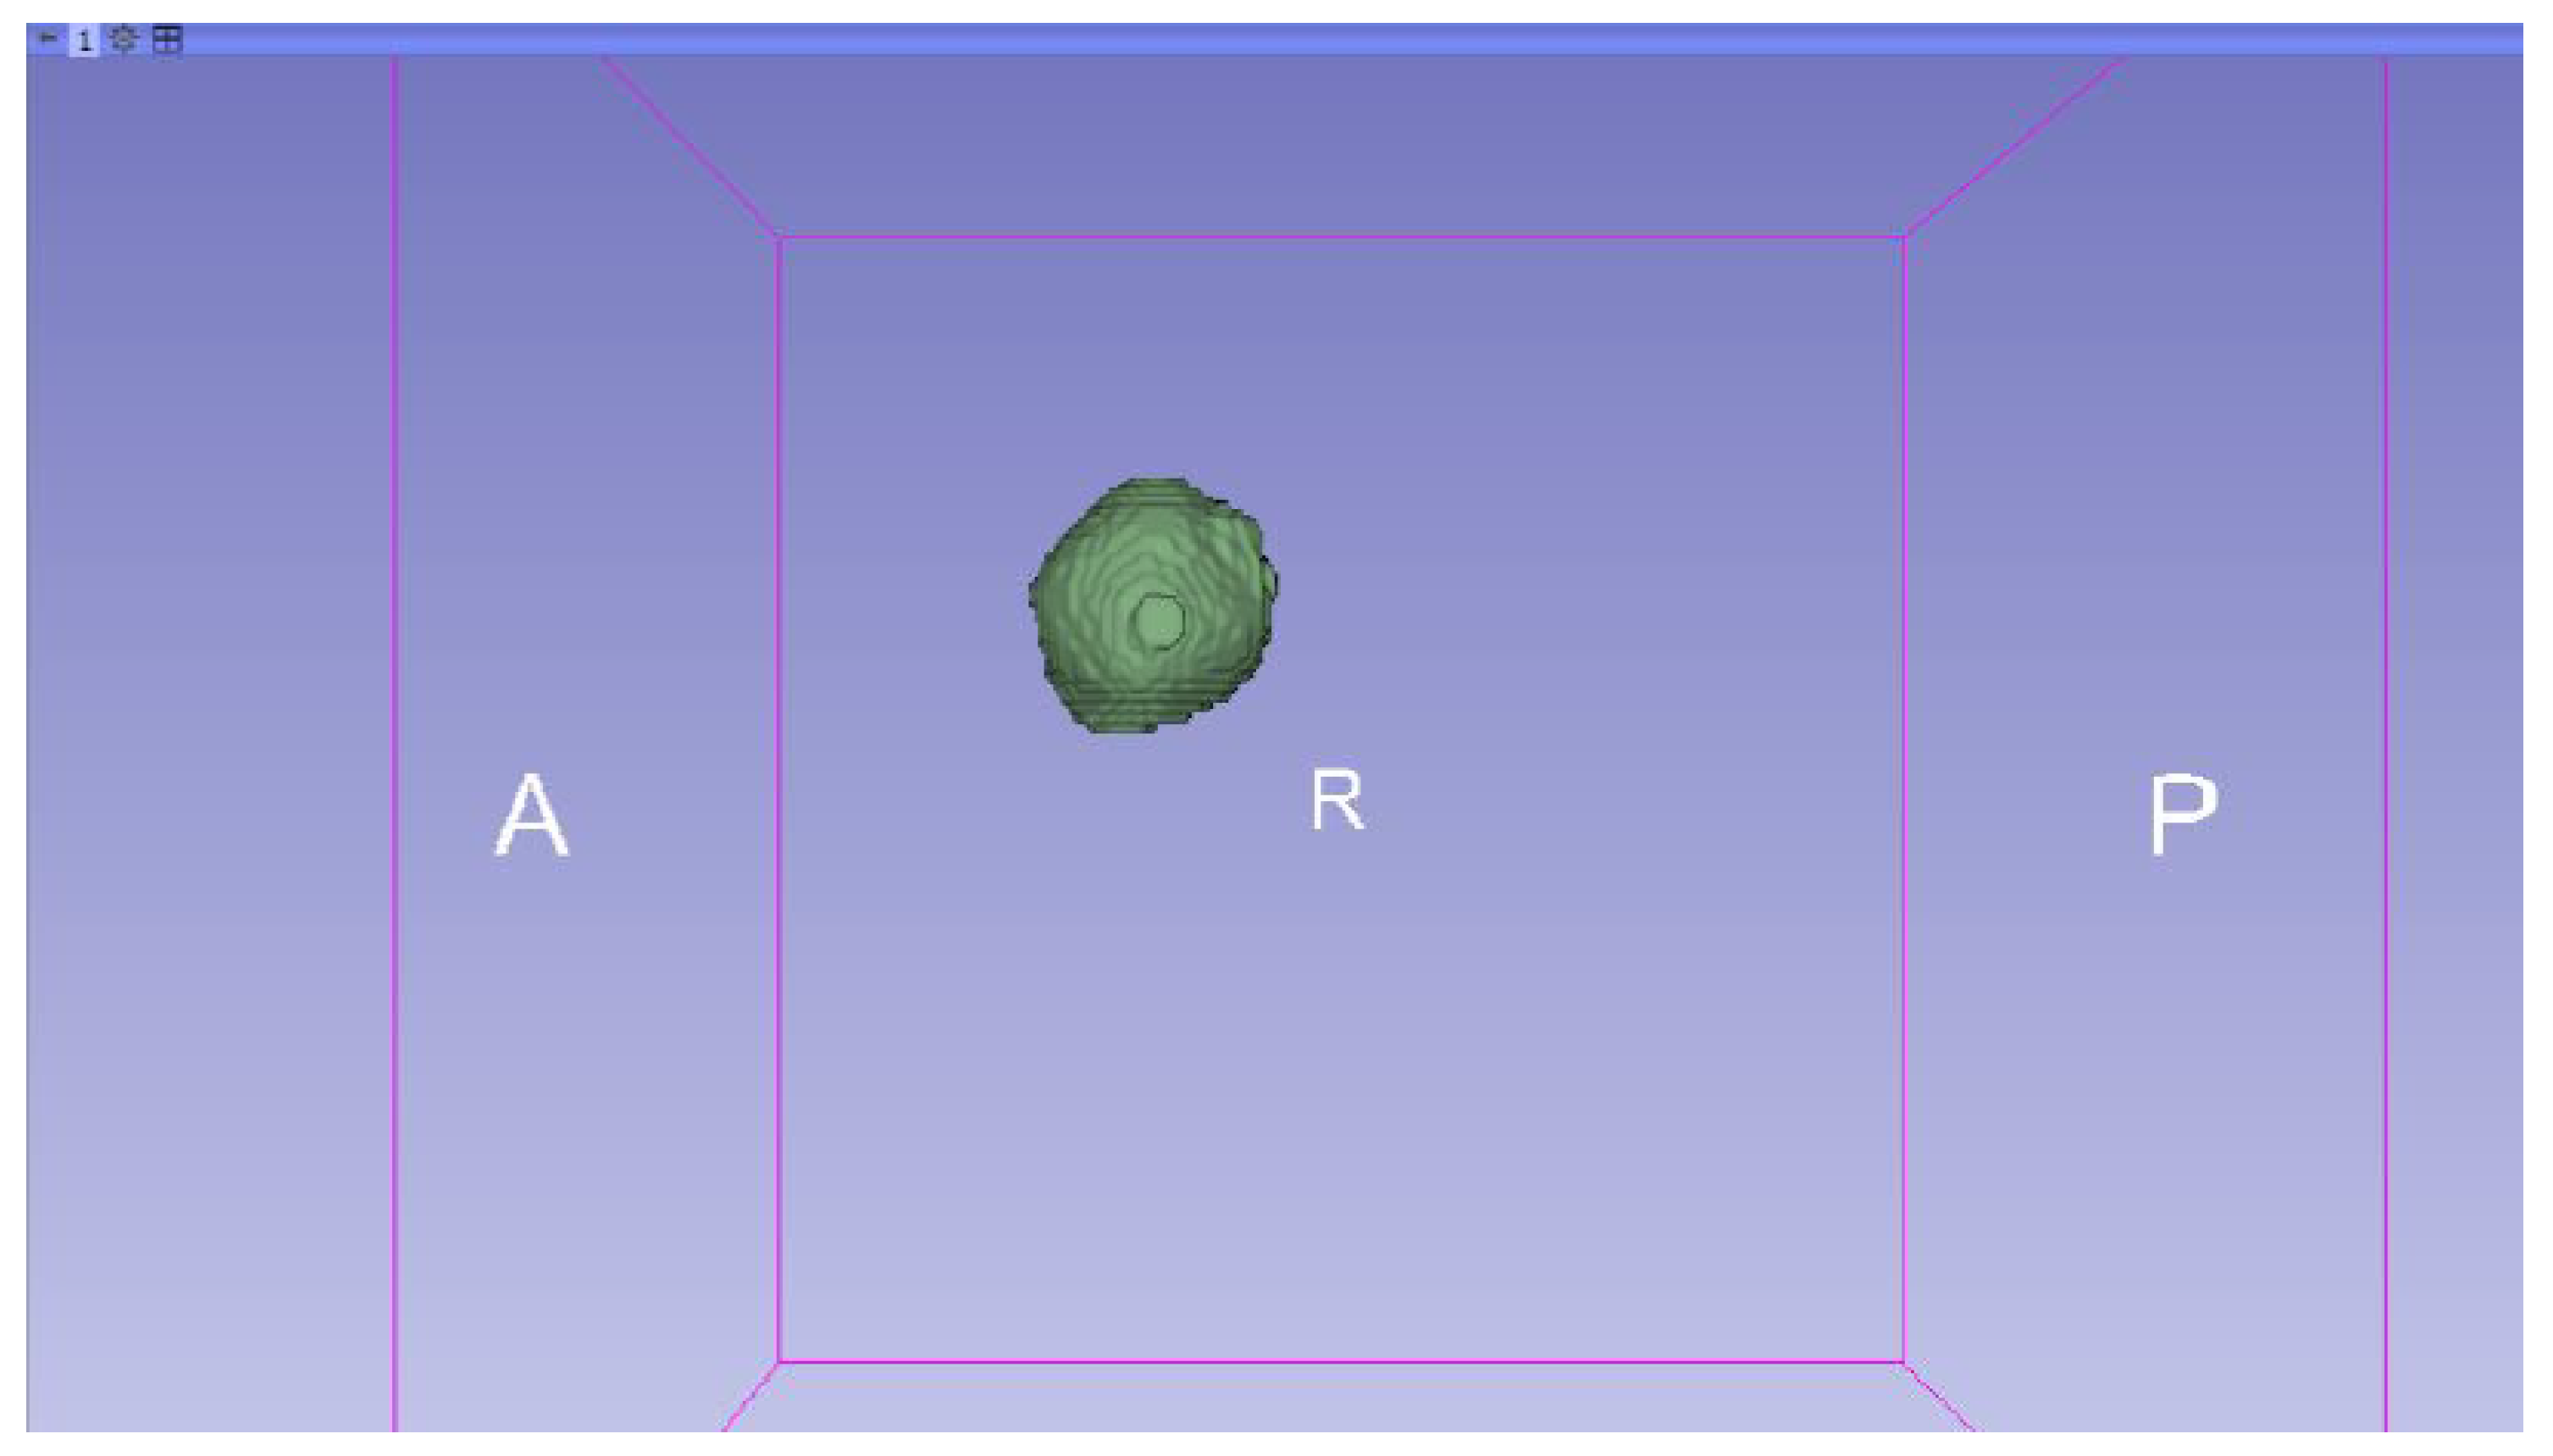

3.3. Human Brain Tumour

3.3.1. DICOM-to-STL Files

- Go to the “Segmentations” Module in the toolbar.

- Go to “Export/import models and label maps”.

- In the menu, select “model” as the output option.

- In “Export to files”, choose the destination folder.

- Select the STL file format, and, finally, click on “Export”.